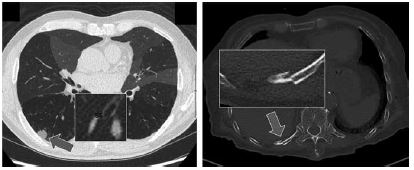

当院に導入されたSAI viewer にはAIを用いたいくつかの診断支援ツールが搭載されているが、その中でもっともよく使うのは肺結節検出のCAD(コンピュータ支援診断)である。ショートカットキーを押して数秒で、肺全体をスクリーニングして結節を検出し、チェックをいれてくれる(図2)。実際には肺野をじっくりみてから、確認のためにCADを走らせる事が多い。感度が高いので必要以上に拾ってしまうのだが、横のバーでは結節のサイズに合わせて矢印も大きくなるので、ある程度取捨選択ができる。少なくともこれで初期の肺転移を見逃す事はないだろう。日常診療における見落とし防止と、読影の負荷軽減に大いに役立っている。